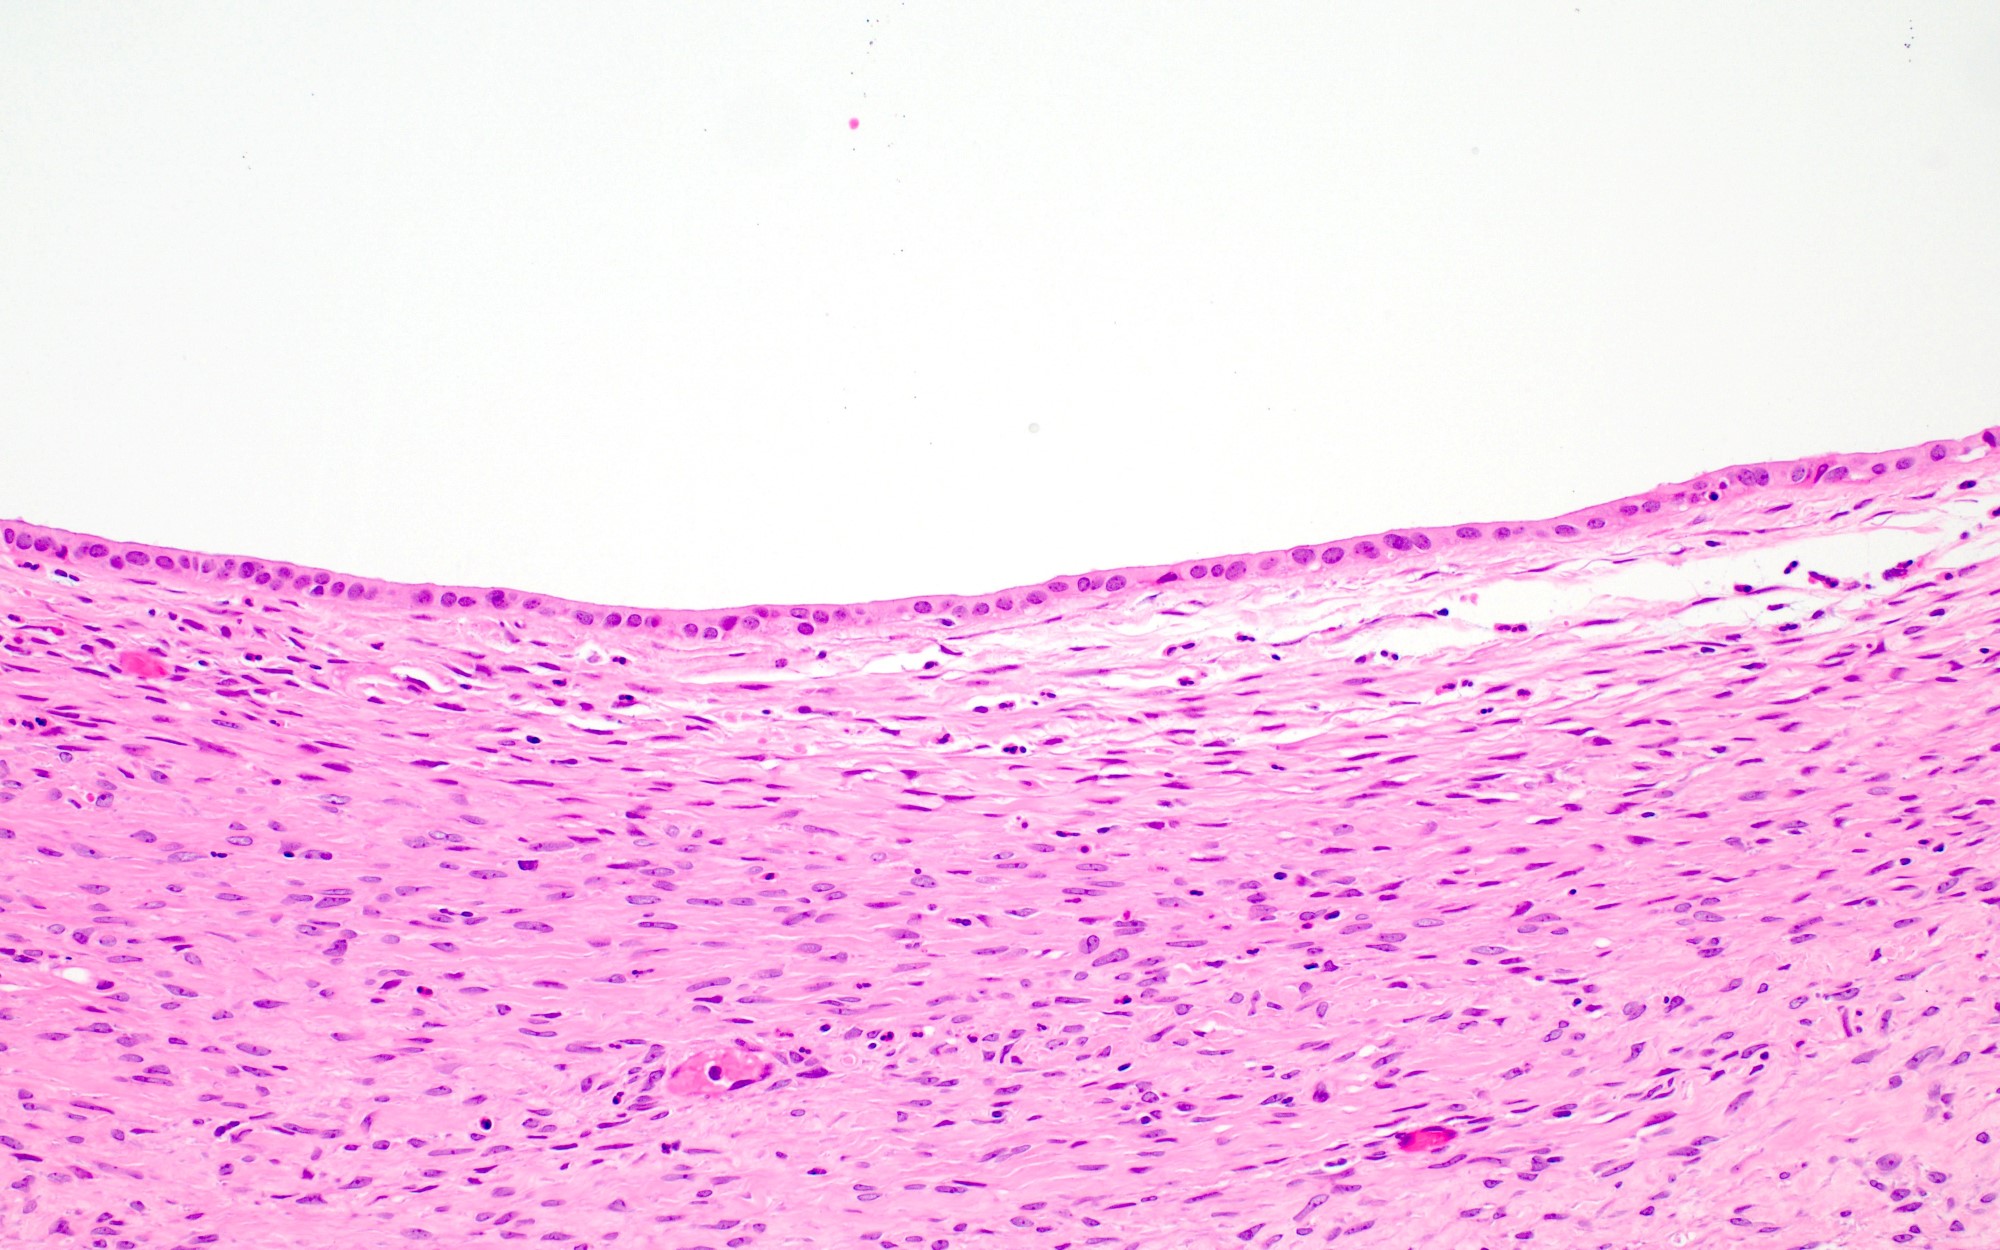

Microscopic (histologic) description

- Cystadenoma:

- Cyst lined by benign endometrioid epithelium without endometrial stroma

- Adenofibroma:

- Widely spaced benign endometrioid glands associated with fibromatous stroma

- Endometriosis may be present

- Areas of mucinous or serous differentiation can be seen (Histopathology 2021;78:445)

Microscopic (histologic) images